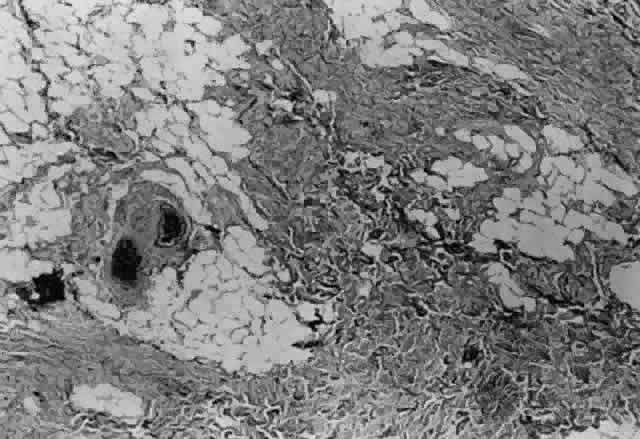

Fig. 18. This fibrous tissue was removed from a patient with prior strabismus surgery. Note the connective tissue component. Thick bands of compact collagenous scar tissue infiltrate orbital fat (hematoxylin and eosin, X 100). (Courtesy of Bruce L. Johnson, MD)

Once the muscle insertion has been “cleaned” of adherent tissue, the distance the muscle is from the original insertion and from the limbus is measured and recorded (Figs. 19 and 20).